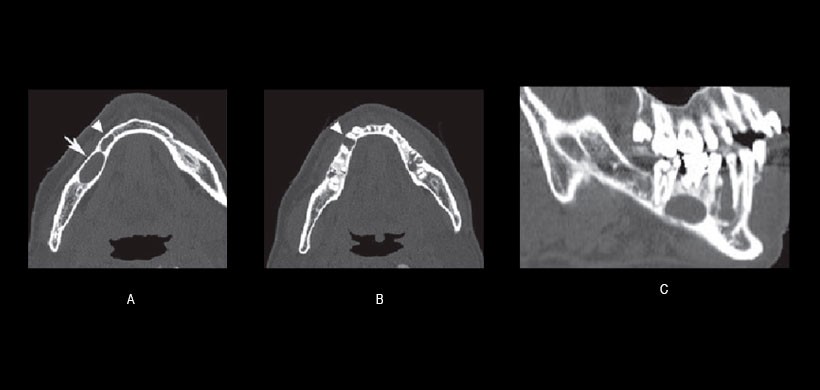

Fig 1. Radiografía panorámica inicial demuestra la presencia de dos lesiones radiolúcidas. Se identificó una lesión alrededor del ápice de la raíz del primer molar inferior derecho (flechas blancas) y se observó otra lesión en el septo interalveolar de los premolares inferior derecho (punta de flecha negra). Los diagnósticos de imagen de las dos lesiones fueron un quiste radicular y un quiste óseo simple, respectivamente.